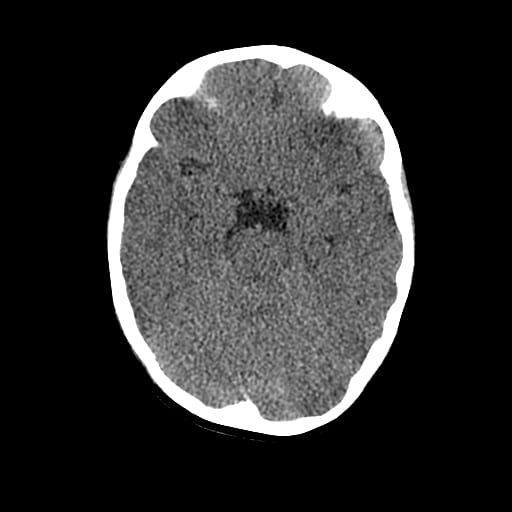

Age: 1

Sex: Male

Indication: Fall